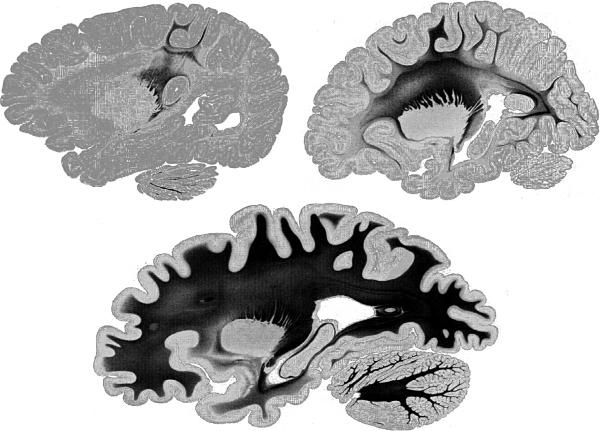

7.2. Разрезы головного мозга человека после окрашивания жира черным красителем. Слева вверху показан головной мозг новорожденного, справа — головной мозг ребенка в детсадовском возрасте, внизу — головной мозг взрослого. У младенца лишь немногие участки соединены посредством быстропроводящих волокон.